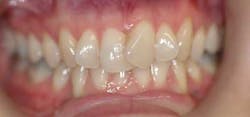

With Cfast, we use ceramic brackets and tooth-colored nickel-titanium wires, so it is very esthetic. An advantage I have enjoyed over the clear tray systems is patient compliance, which is automatic since all the “hardware” is bonded into place. Treatment times are shortened to typically four to seven months. This photo actually shows the author in Cfast: